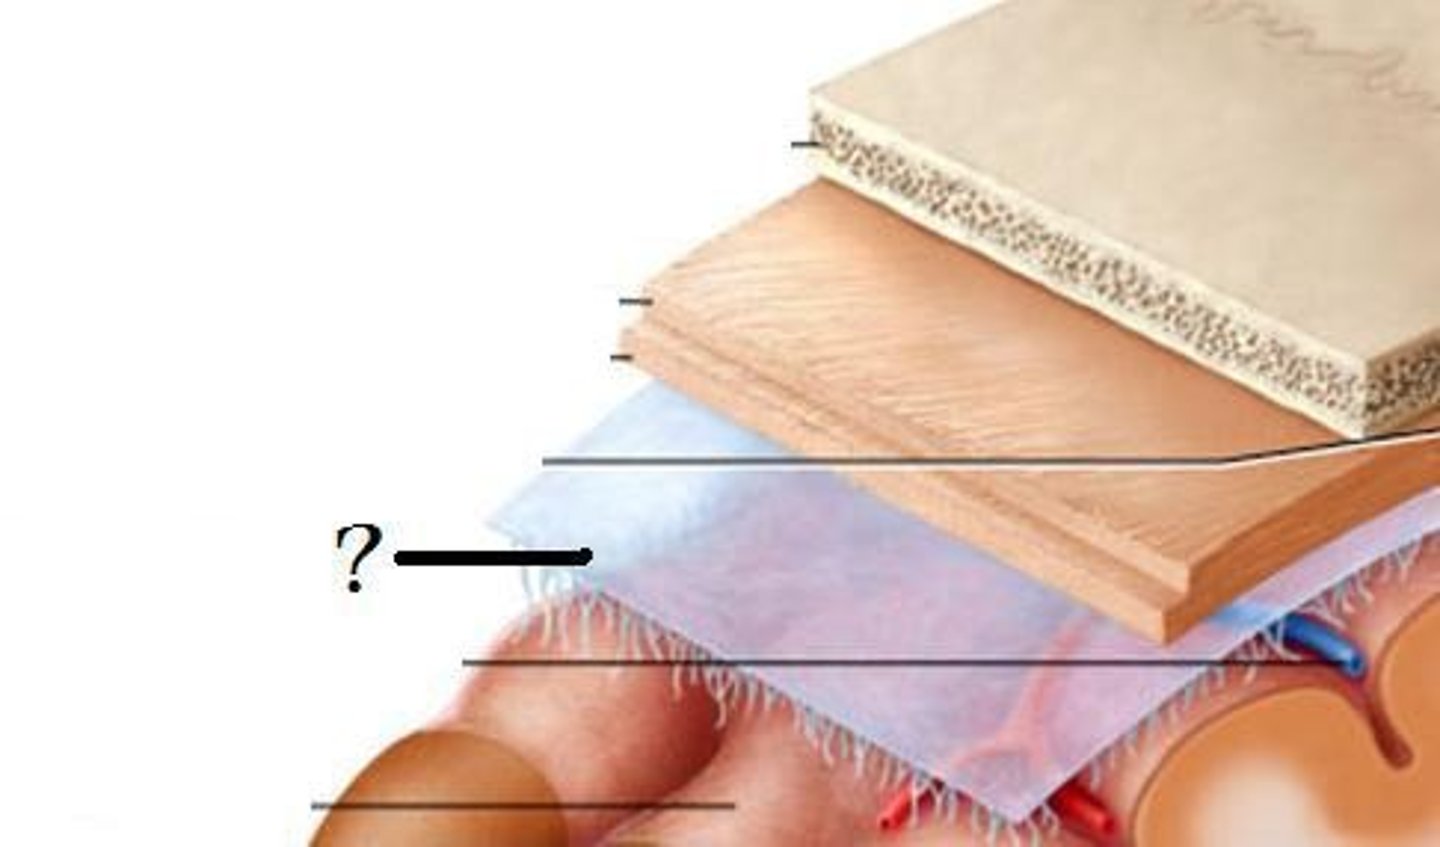

meninges function

protect brain and spinal cord

pia mater

deepest meninge, follows every contour of the brain

arachnoid mater

middle meninge, collagen and elastin fiber, spider web look

dura mater

made up of tough fibrous connective tissue, made up of the periosteal layer (creates periosteum of skull bone)

subarachnoid space

filled with cerebrospinal fluid

subdural space

below the dura mater

potential space (if you have a head injury

the blood goes into the subdural space)